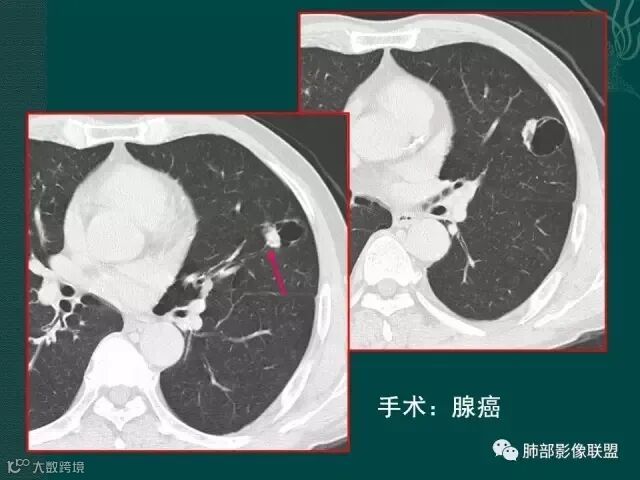

第一个是肺腺癌,边缘有毛刺,多发小空泡,直径不到5mm;

上一个是磨玻璃密度肺癌,边缘清晰,内有分隔,空洞型肺癌伴磨玻璃密度影的,100%为腺癌,很显然这是个假性空洞;

下一个也是肺癌,内有分隔,外下缘箭头所示也是磨玻璃影,这也是腺癌,同时可见叶间裂有转移灶。